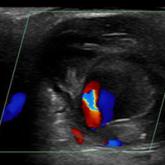

Pulsatile flow is noted through the neck of the mass.

A round pulsatile hand mass with heterogeneous echogenicity.